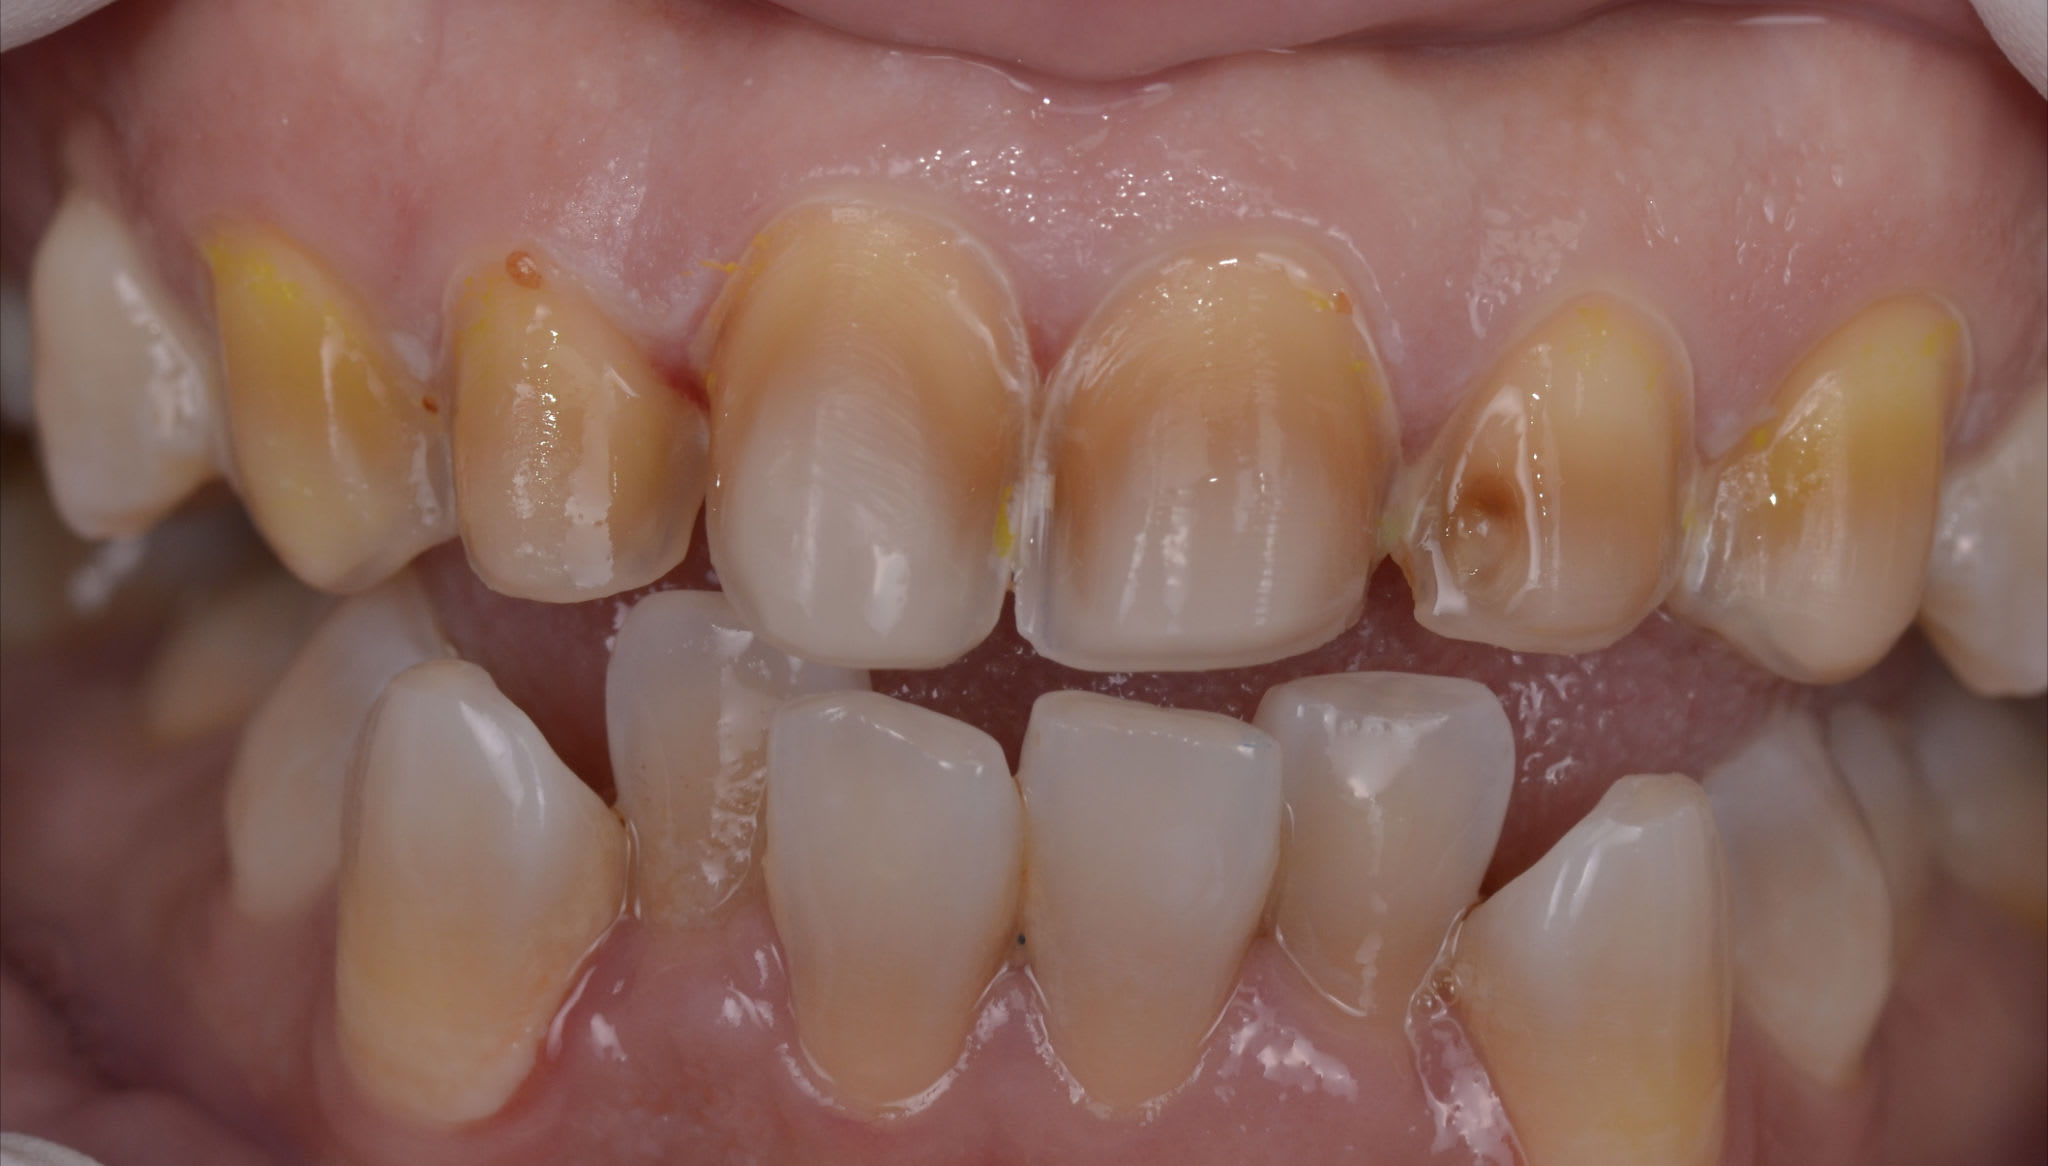

Bon les gars, y a rien là ?

(fait en 2012)

Alors, c'est pas de la déquichisation ça ?

Ai oublié la tof des tailles, pour pas qu'on dise que c'est pas moi qui l'ai fait.